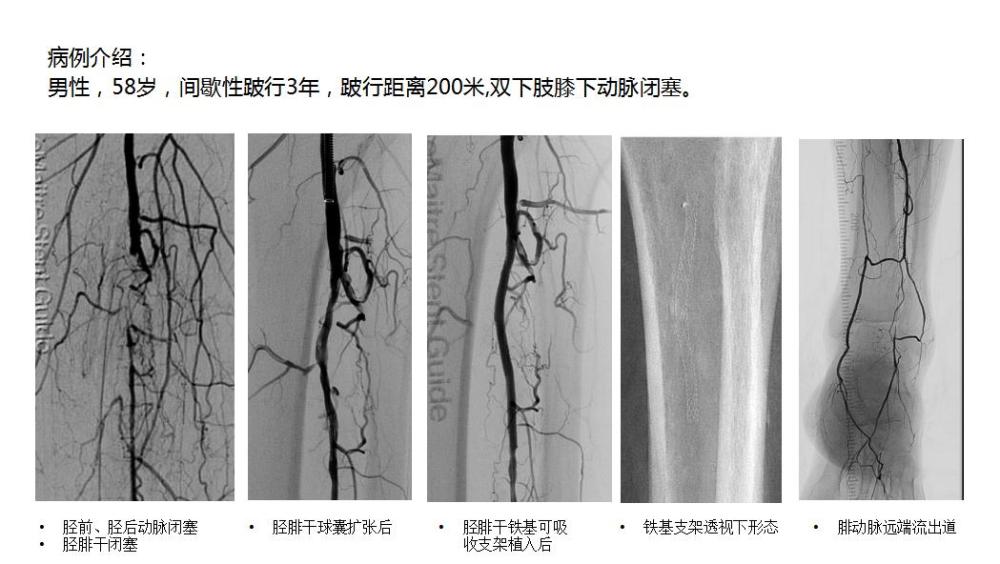

原標題:世界首例全降解鐵基下肢動脈藥物洗脫支架治療膝下動脈閉塞取得成功

新華社北京9月16日電 日前,解放軍總醫(yī)院第一醫(yī)學(xué)中心血管外科郭偉教授團隊成功實施了世界首例全降解鐵基下肢動脈藥物洗脫支架(IBSTitan)治療膝下動脈閉塞癥。

本例手術(shù)的成功實施標志這款產(chǎn)品正式進入臨床研究,期待這款中國創(chuàng)造的器材能夠取得好的臨床結(jié)果。